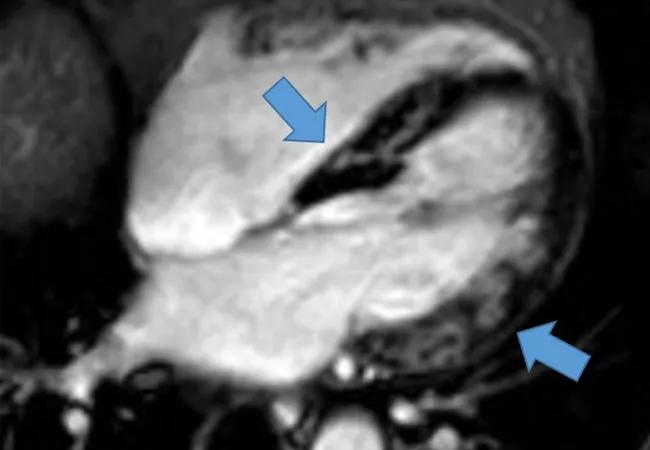

Cardiac-MRI-w-Arrows-650x450pxl

Attending the 2018 American Thoracic Society (ATS) International Conference? Spend an early morning learning the diagnosis and management of two very challenging manifestations of sarcoidosis neurologic and cardiac with Cleveland Clinic staff pulmonologist Manuel Ribeiro Neto, MD. This Sunrise Seminar will include case-based discussion and an overview of current evidence.